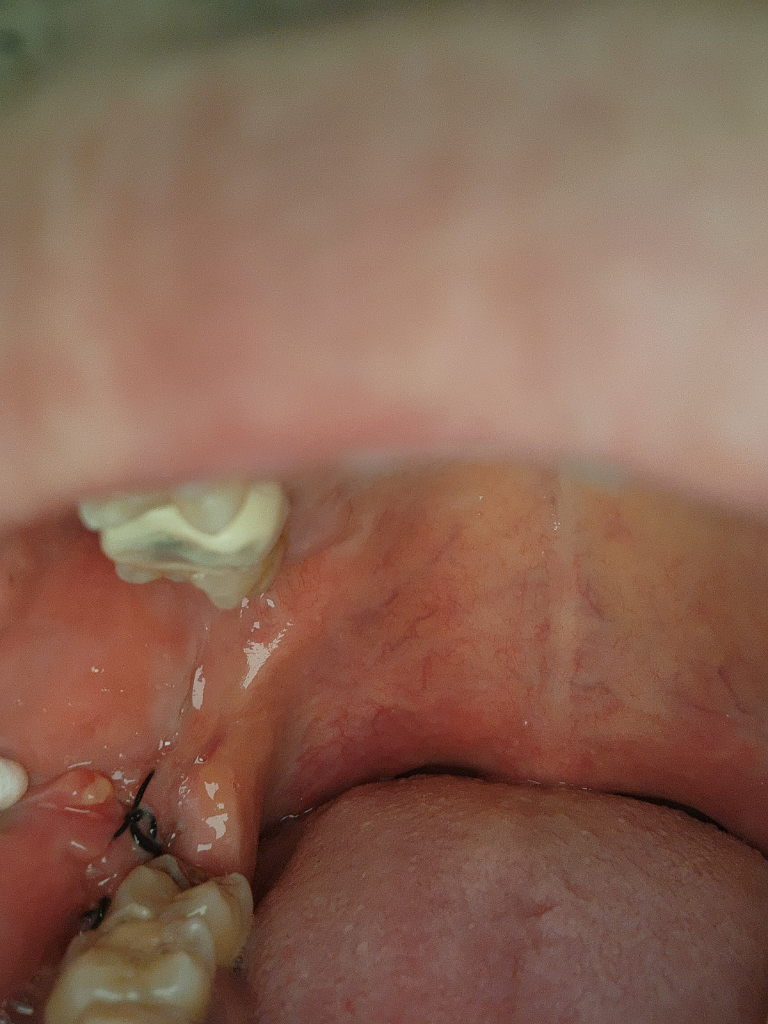

사진으로는 정확한 확인을 하기 힘들어 보입니다. 자세한 확인을 위해선 치과에서 진료를 받아보는 것이 좋으며 발치 한 부위가 잘 아물기 위해서는 해당 부위를 자극하지 않는 것이 좋습니다

사진으로 잘 낫고 있는 것으로 보이며 통증도 없고 붓기도 없다면 염증의 가능성은 낮습니다.

사진상으로 보면 발치하신곳이 잘 아물고 잇는거 같습니다. 지금처럼 관리하시고 실밥을 빼시면될것같습니다.

현재 사진상 해당부위가 잘아물고 있는 것으로 보이며, 7일간은 염증이 덧나지 않도록 음주 및 흡연은 피하길 권합니다.

사진상으로 특별히 문제점은 없는 것 같습니다. 1주일정도는 발치 후 주의사항 잘 지키시면 되겠고, 다음 봉합실 푸는 약속 맞춰서 가셔서 소독 받으시고, 봉합실 정리하면 되겠습니다.